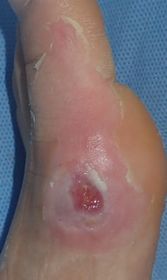

7歳男。

2015年10月26日夕方,自転車に乗っていて車と接触し転倒。左足内側に怪我。直ちに当院ERを受診し,プラスモイストで治療。

翌日,当科を受診。左第1趾MTP関節部に直径2センチ大の全層皮膚欠損あり。プラスモイストで被覆。

| 10月27日 | 10月29日 | 11月6日:10日後 | 11月13日:17日後 |